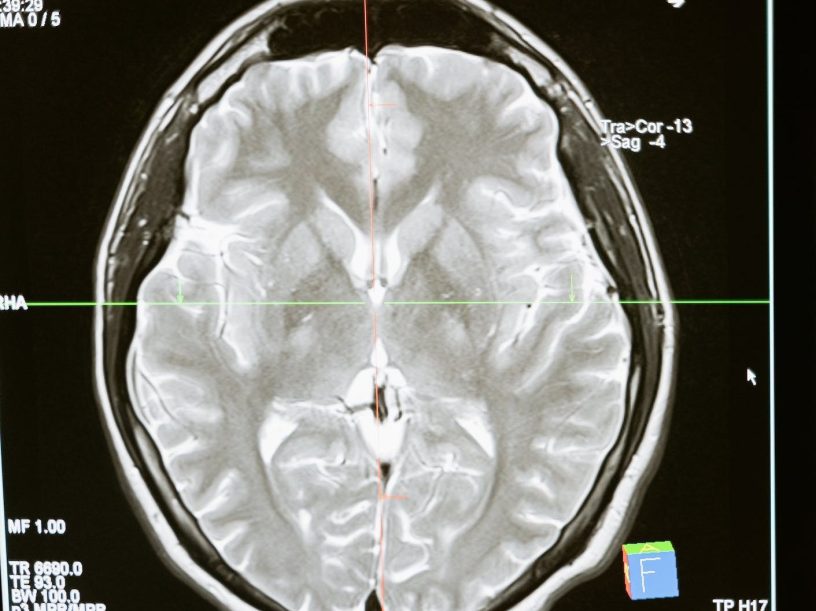

Despite regular MRI scans showing the tumour was growing and was pushing her brain to one side, she was told that it was not growing and was not offered surgery to remove it until May 2015.

(Pic is via Pexels and generic)